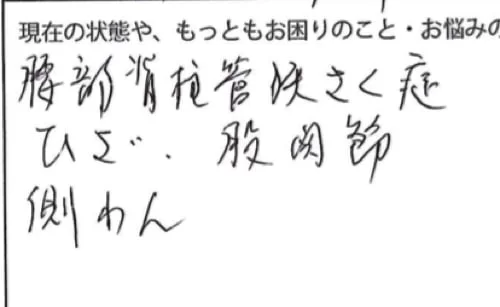

整形外科では脊柱管狭窄症と診断されていたそうで

膝に違和感もあり、正座が出来ず、股関節の辺りも氣になっているそうです。

側弯症もあるとのことでした。

本日 痛みのある場所はこの足首辺りから足の甲にかけてと

腰はこの辺りが痛いそうです。